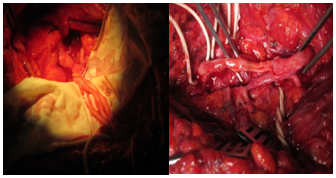

Nerve grafting technique: Three patients underwent nerve grafting as follows: in case 2 and 10, neuroma was found in the lateral cord, resection, and grafting using sural nerve was done. (Figure 4 & 5) In case 6, neuroma was found in the lateral cord and ulnar nerve, resection and grafting was done using the sural nerve.

Figure 4&5 Intraoperative pictures showing the sural nerve while being cabled and used in grafting (Suez Canal University Hospital, Ismailia, Egypt).